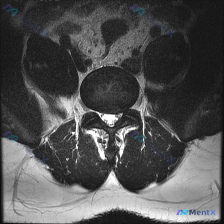

今天整理了一份只有单张腰椎MRI T2加权轴位片的椎间盘病变分析案例,跟大家分享一下读片和临床分析的思路。 病例影像基本信息 本次仅提供单张腰椎MRI T2加权轴位图像,具体读片发现如下: 1. 节段定位:根据椎体、椎弓根和关节突形态判断,该切面位于腰椎,最可能为L4/5或L5/S1水平 2. 椎间...

收到一份腰椎MRI单张轴位片,临床怀疑椎间盘病变,整理一下读片思路和分析,和大家交流。 一、影像基本信息 这是一张腰椎MRI T2加权轴位扫描图像,我们逐层拆解结构: 1. 椎体与终板:椎体后缘信号正常,低信号符合皮质骨表现,没有明显骨质破坏、水肿,也没有典型Modic终板炎改变 2. 椎间盘:髓核...